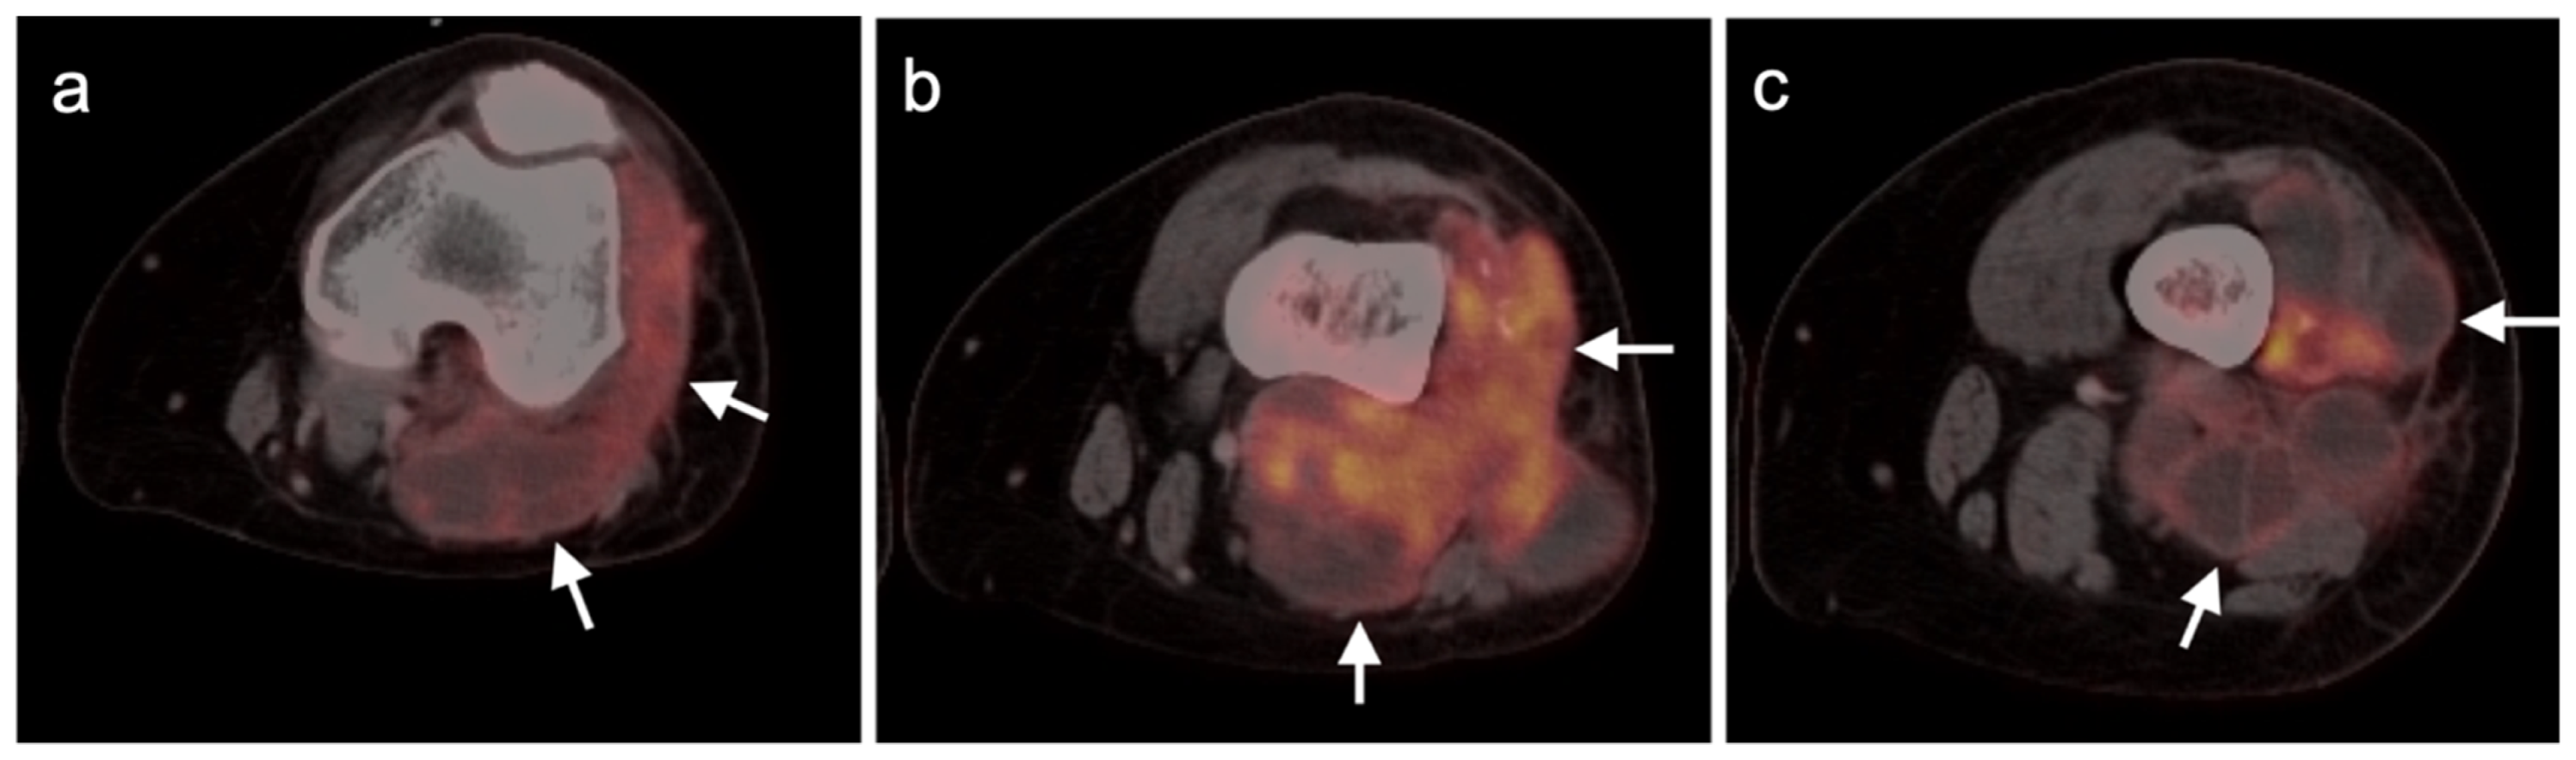

- Schuetze, S.M.; Rubin, B.P.; Vernon, C.; Hawkins, D.S.; Bruckner, J.D.; Conrad, E.U.; Eary, J.F. Use of positron emission tomography in localized extremity soft tissue sarcoma treated with neoadjuvant chemotherapy. Cancer 2005, 103, 339–348. [Google Scholar] [CrossRef] [PubMed]

- Benz, M.R.; Czernin, J.; Allen-Auerbach, M.S.; Tap, W.D.; Dry, S.M.; Elashoff, D.; Chow, K.; Evilevitch, V.; Eckardt, J.J.; Phelps, M.E.; et al. FDG-PET/CT Imaging Predicts Histopathologic Treatment Responses after the Initial Cycle of Neoadjuvant Chemotherapy in High-Grade Soft-Tissue Sarcomas. Clin. Cancer Res. 2009, 15, 2856–2863. [Google Scholar] [CrossRef] [PubMed] [Green Version]